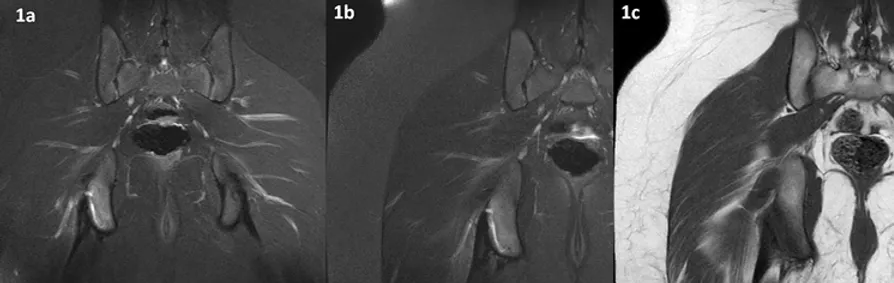

Figura 1 (a-c): Imagens de RM no plano coronal da bacia na ponderação T2 com supressão de gordura (1a) e do quadril direito nas ponderações T2 com supressão de gordura (1b) e T1 (1c).

Figura 1 (a-c)’: Imagens de RM no plano coronal da bacia na ponderação T2 com supressão de gordura (1a’) mostrando pequena quantidade de líquido (seta amarela) entre os tendões isquiotibiais (seta verde) e a tuberosidade isquiática à direita onde há edema ósseo (setas azuis). Na imagem ampliada do quadril direito na ponderação T2 com supressão de gordura (1b’) é possível identificar que houve pequena avulsão da tuberosidade isquiática (seta branca) na origem dos tendões isquiotibiais (seta verde) com pequena quantidade de líquido entre a tuberosidade e o fragmento (seta amarela). Na ponderação T1 (1c’) nota-se o baixo sinal no ísquio pelo edema ósseo (setas azuis).